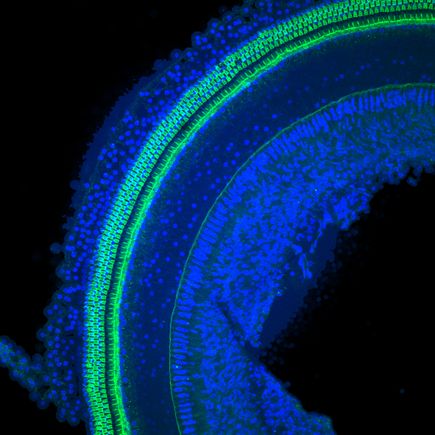

Seeking to stem the tide of permanent hearing loss from the use of lifesaving antibiotics, researchers at Oregon Health & Science University have found that patients stricken with dangerous bacterial infections are at greater risk of hearing loss than previously recognized. Inflammation from the bacterial infections substantially increased susceptibility to hearing impairment by increasing the uptake of aminoglycoside antibiotics into the inner ear, the researchers report. Their findings are published in online in the journal Science-Translational Medicine.

Aminoglycosides, antimicrobials that are indispensable to treating life-threatening bacterial infections, are toxic to the ear. Relied on by physicians to treat meningitis, bacteremia and respiratory infections in cystic fibrosis, aminoglycosides kill the sensory cells in the inner ear that detect sound and motion.

When Steyger and colleagues gave healthy mice a low amount of aminoglycoside, the rodents experienced a small degree of hearing loss. If the mice had an inflammation that is typical of the infections treated with aminoglycosides in humans, the mice experienced a vastly greater degree of hearing loss.